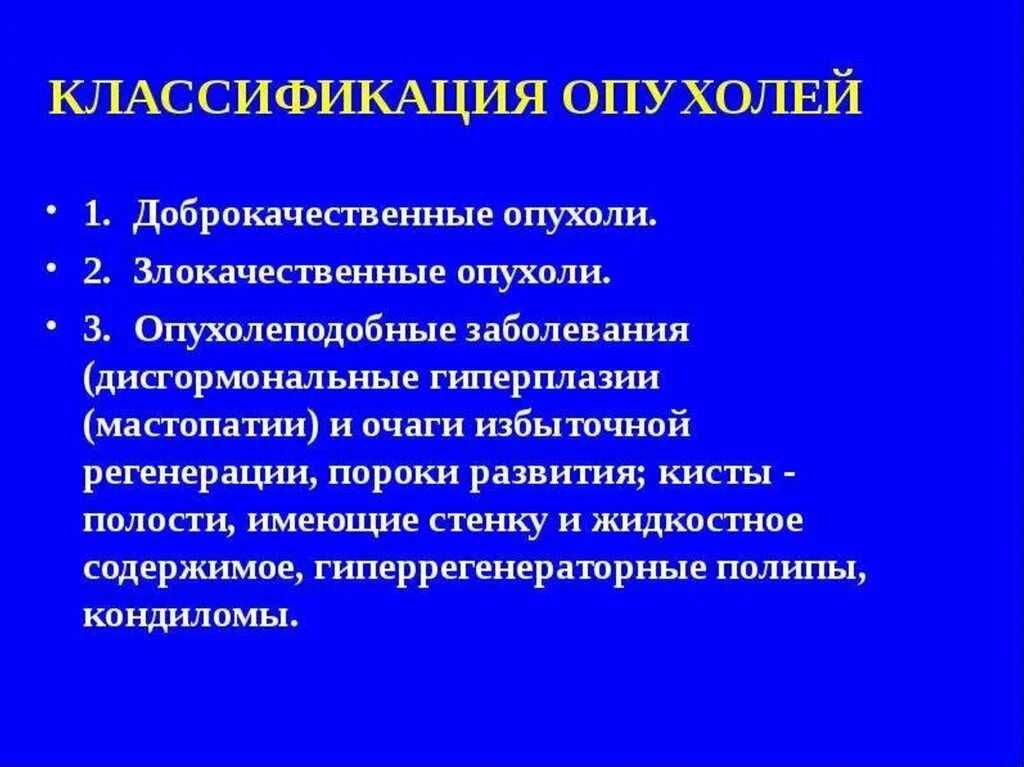

Мрт головного мозга с контрастированием. Мрт с контрастированием опухоль. Мрт головы с контрастом. Магнитно резонансная томография с контрастом головного мозга. Классификация опухолей. Классификация новообразований. Классификация опухолей по воз. Классификация воз опухолей костей.

Классификация опухолей. Классификация новообразований. Классификация опухолей по воз. Классификация воз опухолей костей. Опухоли головки поджелудочной железы классификация. Доброкачественная опухоль поджелудочной. Доброкачественная опухоль поджелудочной железы. Гистологическая классификация опухолей поджелудочной железы.